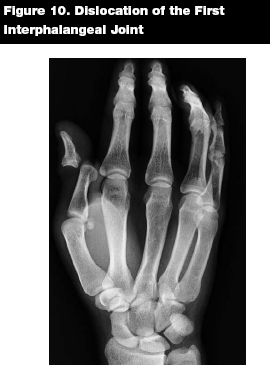

Epidemiology. The interphalangeal (IP) joints of the fingers are the most commonly dislocated joints in the body.15 Dislocations of the interphalangeal joint of the thumb, however, are uncommon.13

Patterns of Injury. Trauma and athletic injuries are common causes of IP joint injuries. Most IP joint dislocations are dorsal, meaning that the more distal bone is dorsally displaced in relation to the proximal bone. Lateral dislocations also commonly occur. Rarely, the distal bone will be displaced toward the palmar aspect of the hand, producing the uncommon volar IP joint displacement.25

Management. Dorsal dislocations are reduced with distal traction and pressure in a volar direction to the dislocated bone. (See Figures 9 and 10.) Digital nerve block allows for a painless reduction, but may not be necessary if the patient presents less than one hour after dislocating the joint.15 After relocating the joint, the affected digit should be splinted or buddy taped to the adjacent finger.

![]() |

Volar dislocations can be more difficult to reduce in the ED, and may require consultation with the hand surgeon. Reduction may be attempted with distal traction and dorsal pressure on the dislocated bone.26 Assuming a successful reduction, the subspecialist will typically splint the injured digit in extension for six weeks.15

Key Points. Dorsal IP dislocations are more common than volar IP dislocations. Pre- and post-reduction radiographs should be obtained. Splint the affected digit after reduction. Volar dislocations may require referral to a hand surgeon for definitive management.